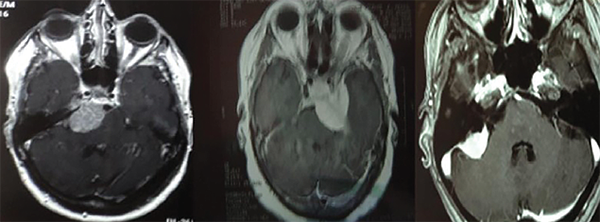

Por definición, los meningiomas petroclivales tienen su origen medial a los pares craneales V, VII, VIII, IX, X y XI, y pueden alcanzar el tentorio.1,3,5,6 A menudo se extienden hacia la fosa media, el seno cavernoso y la cisterna prepontina (Figura 1). Pueden descender al agujero magno, pudiendo invadir la piamadre y causar compresión del tronco encefálico. En los casos en que hay edema del tronco encefálico (hipodensidad en la tomografía o hiperseñal enT2 en la resonancia magnética) o una forma dentada e irregular del tumor sobre el tejido cerebral, la extracción total es muy difícil o imposible sin causar déficits neurológicos3-5(Figura 2). Los meningiomas del clivus inferior (foramen magno), petrosos, tentoriales y del ala esfenoidal pueden alcanzar estas áreas, pero no se consideran de origen petroclival.6

Figura 1: Resonancia magnética axial en T1 con gadolinio. Meningioma petroclival (izquierda), meningioma esfenopetroclival (centro), meningioma petroso (derecha).